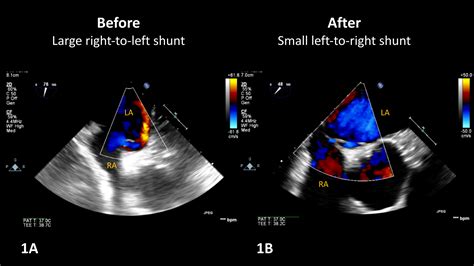

Understand the mechanics of a Right to Left Shunt, a serious cardiac condition where deoxygenated blood bypasses the lungs. Learn about common congenital heart defects, clinical symptoms like cyanosis, and essential diagnostic procedures. This expert guide clarifies the causes, health risks, and treatment options for managing abnormal blood flow patterns and ensuring proper systemic oxygenation.

TitleIntraoperative hypoxemia and dynamic right-to-left shunting across a patent foramen ovale ...